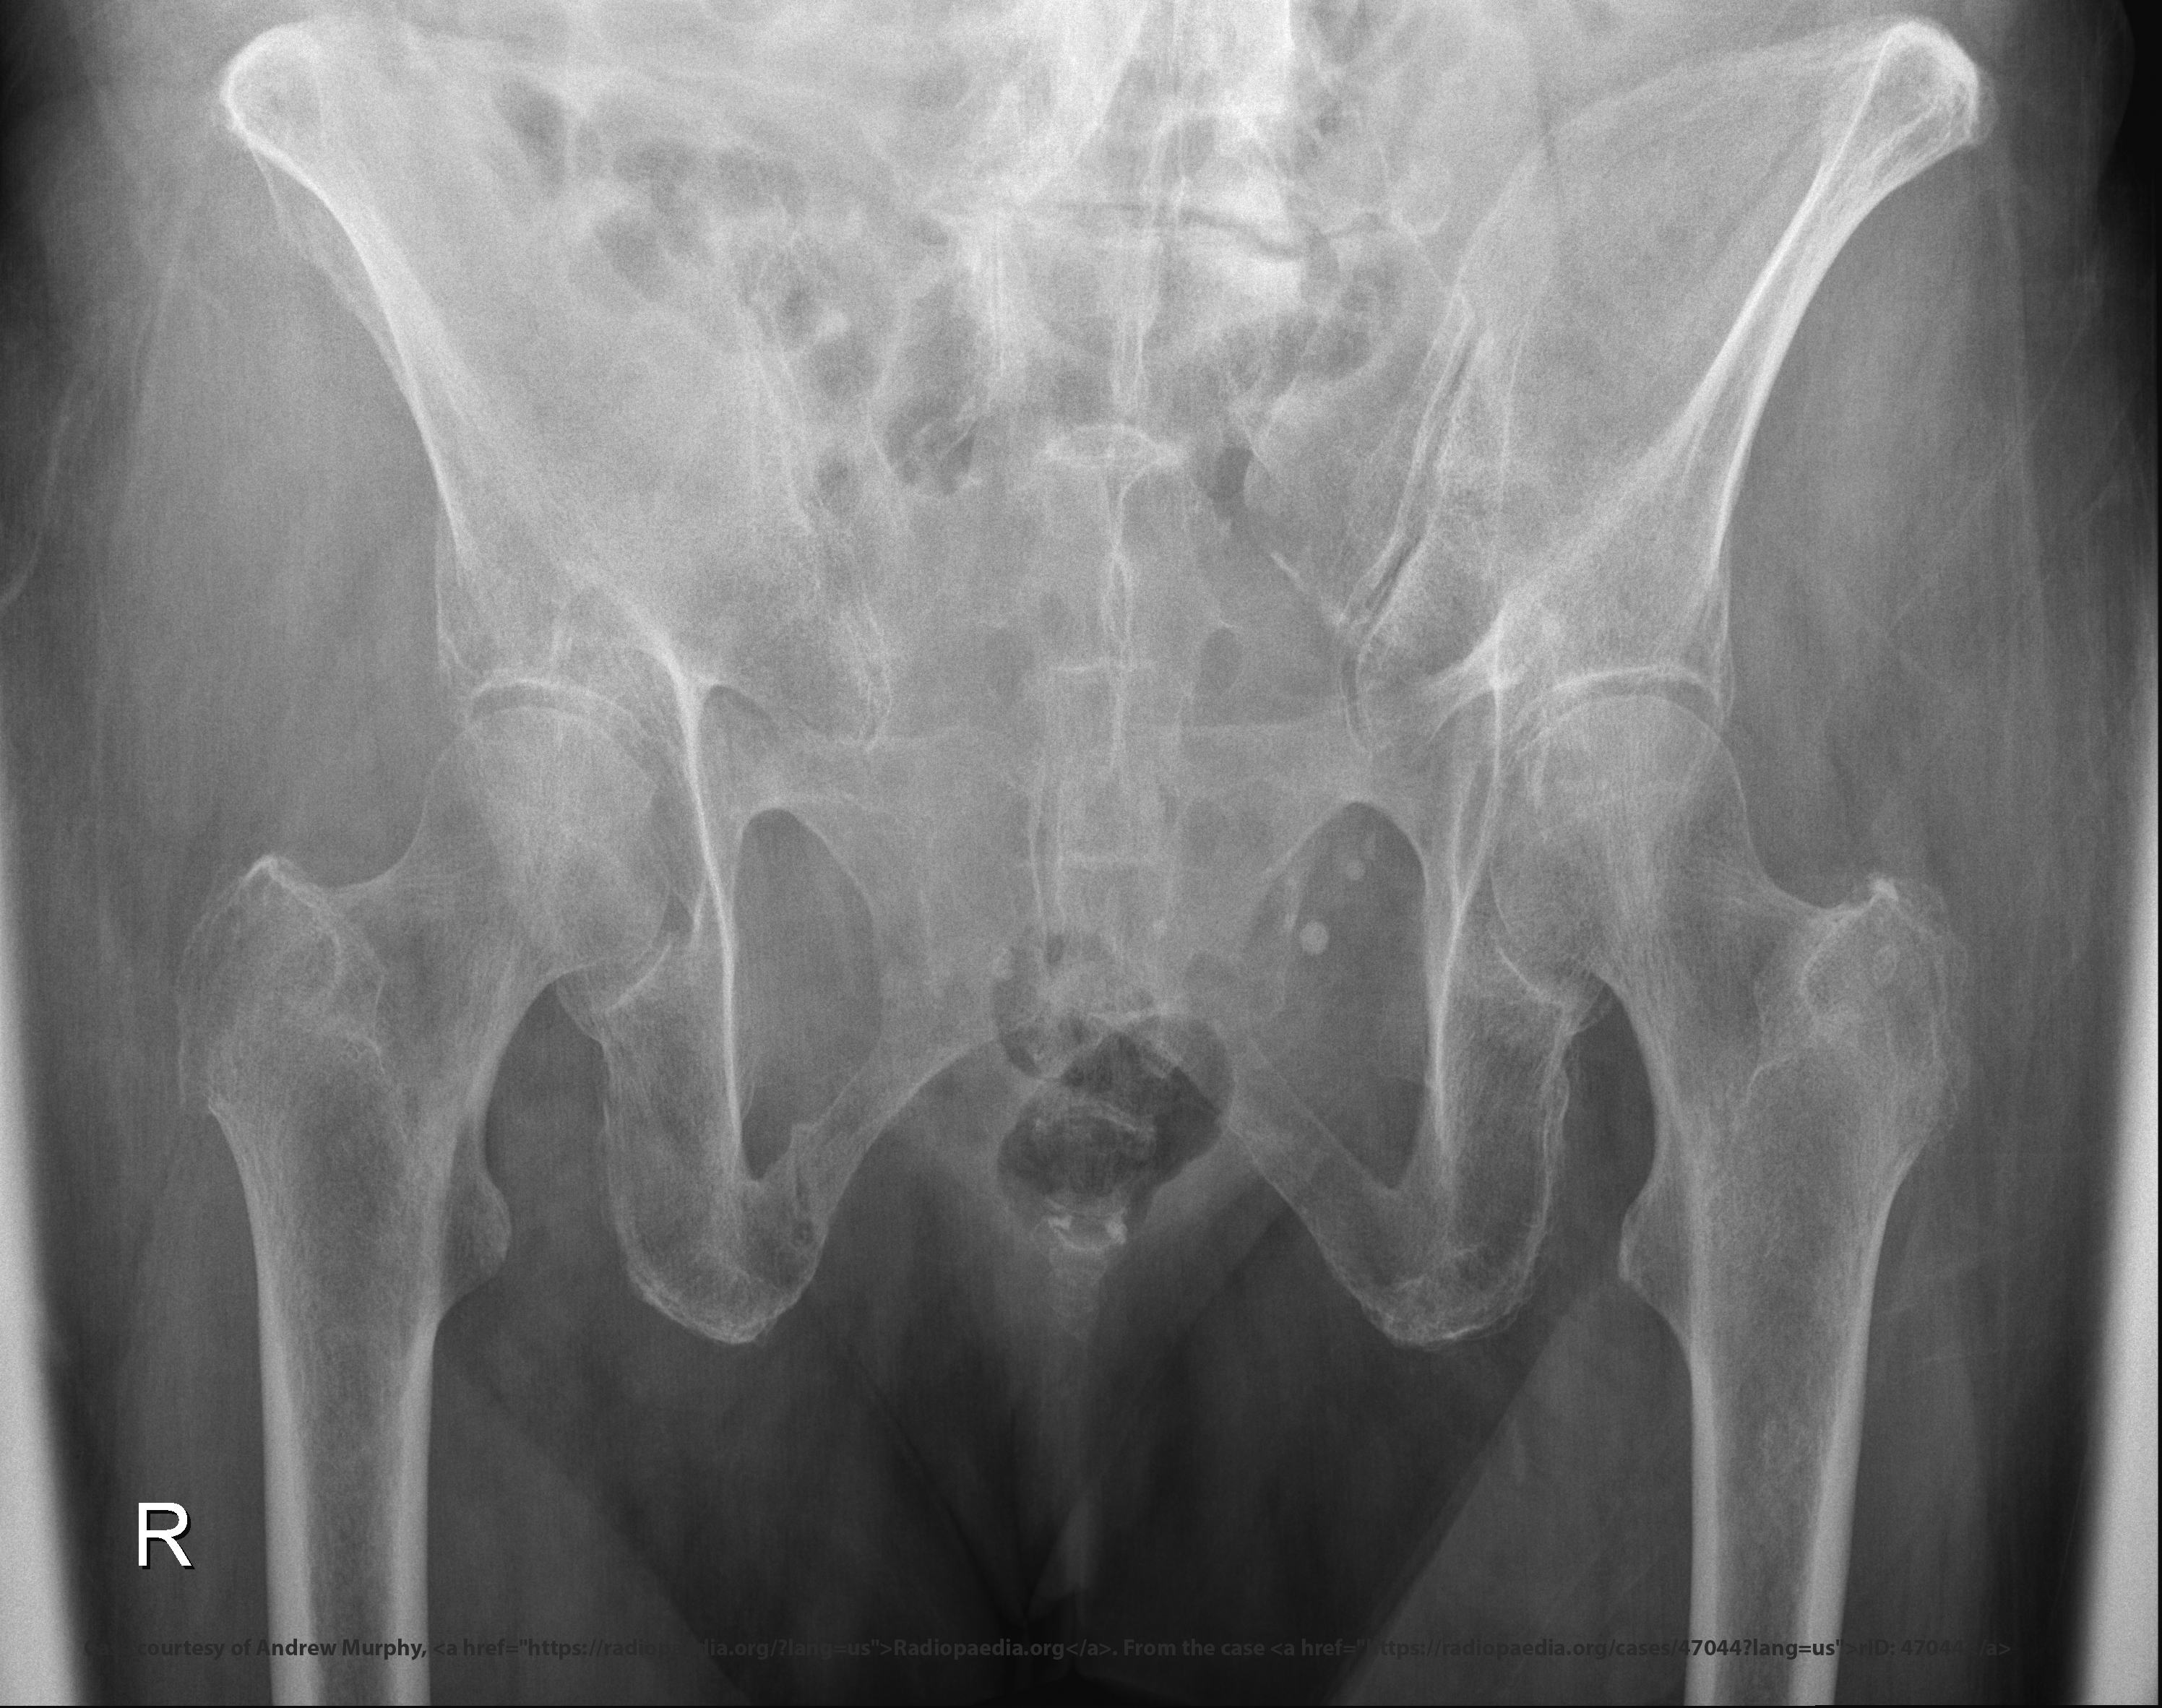

What indicates no rotation in an AP axial SI joint projection?

Symmetric SI joints.

<p>Symmetric SI joints.</p>